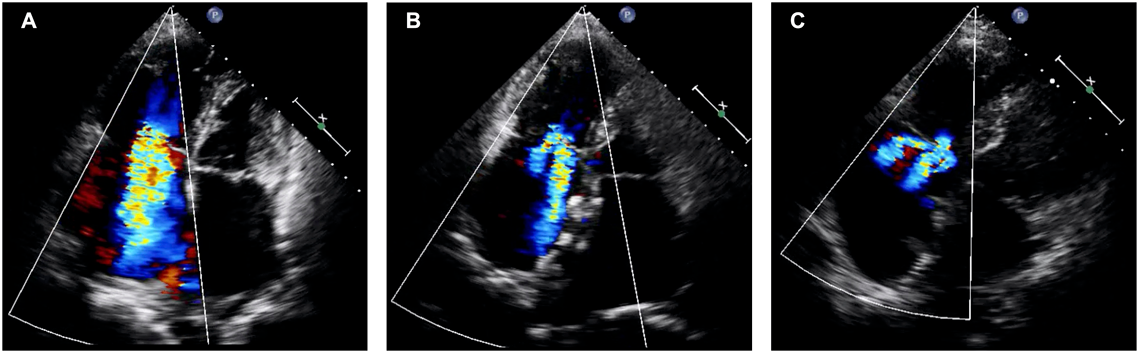

心不全を増悪させる因子として,弁膜症も重要である.特に成人期に診断されるASDでは長年の負荷により右心系は拡大し,それに伴い三尖弁輪の拡大と三尖弁閉鎖不全症(Tricuspid regurgitation, TR)を認めることが多い.中等度以上のTRを合併した症例では原則として外科的ASD閉鎖術の適応である.しかし,経カテーテルASD閉鎖術でも閉鎖術後に右室拡大は改善し,TRが軽減することが報告されている(Fig. 310).さらに,閉鎖術前に重症TRであった症例でも軽症TRと予後が変わらないことも併せて報告されており,今後はTRを合併した症例でも,経カテーテルASD閉鎖術が治療選択肢に入る可能性はある.

Fig. 3 経カテーテルASD閉鎖術前後でのTRの変化

(A)ASD閉鎖術前では右心系の拡大に伴う三尖弁輪径の拡大と,重症のTRを認めた.(B)経カテーテルASD閉鎖術1か月後では,右心系の縮小に伴い三尖弁輪径も縮小し,TRも中等度程度まで改善した.(C)経カテーテルASD閉鎖術3年後には,さらに右心系は縮小し,TRも軽度まで改善を認めた.ASD=atrial septal defect; TR=tricuspid regurgitation